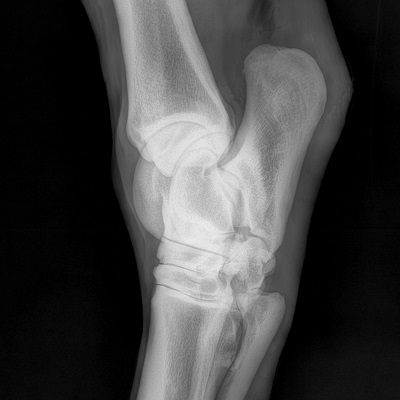

hock radiograph